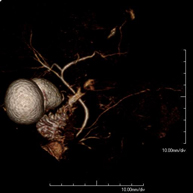

Prueba diagnóstica no invasiva que consiste en la obtención de imágenes de alta definición anatómica de todo el cuerpo mediante el empleo de un campo electromagnético y ondas de radio (con un emisor y un receptor). No utiliza radiación ionizante. Es una prueba muy importante en la búsqueda de metástasis en pacientes con neoplasia conocida. No requiere preparación previa. No es necesario el empleo de contraste paramagnético (Gadolinio). - Angio-RM Aorta abdominal

Prueba diagnóstica no invasiva que consiste en el estudio de la arteria aorta abdominal, obteniendo imágenes de alta definición anatómica mediante el empleo de un campo electromagnético y ondas de radio (con un emisor y un receptor). Es indispensable el uso de contraste paramagnético (Gadolinio). Sin embargo, no utiliza radiación ionizante. La calidad de las imágenes permite realizar reconstrucciones en 2D y 3D. Está indicado en aquellos pacientes con enfermedad vascular (aterosclerosis), estudio de aneurismas, en estudios pre-quirúrgicos de lesiones adyacentes a la aorta abdominal como "mapa" vascular, etc. - Angio RM Aorta-ilíaca

Prueba diagnóstica no invasiva que consiste en el estudio de las arterias renales, obteniendo imágenes de alta definición anatómica mediante el empleo de un campo electromagnético y ondas de radio (con un emisor y un receptor). Es indispensable el uso de contraste paramagnético (Gadolinio). Sin embargo, no utiliza radiación ionizante. La calidad de las imágenes permite realizar reconstrucciones en 2D y 3D. Esta prueba está indicada por ejemplo en aquellos pacientes que sufren de HTA refractaria al tratamiento, en pacientes con lesiones renales para tener un mapa "vascular" pre-quirúrgico, etc. - Entero-RM